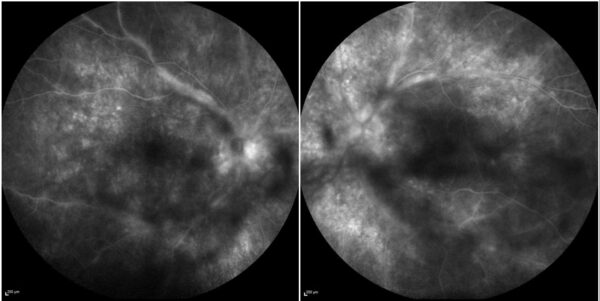

Spectral-domain optical coherence tomography (SD-OCT) was consistent with bilateral subclinical optic disc edema. Enhanced depth imaging (EDI) OCT detected significantly increased choroidal thickness, respectively 700 μm in the right eye (RE) and 750 μm in the left eye (LE). Fundus fluorescein angiography (FFA) revealed numerous pinpoint hyperfluorescent spots and optic nerve head edema, periphlebitis, and diffuse capillary leakage in BE, more pronounced on the left (Figure 2).

Figure 2: FFA (Spectralis, Heidelberg Engineering®) showing multiple pinpoint hyperfluorescent spots and diffuse capillary dye leakage, along with periphlebitis and a “hot disc” in both eyes.